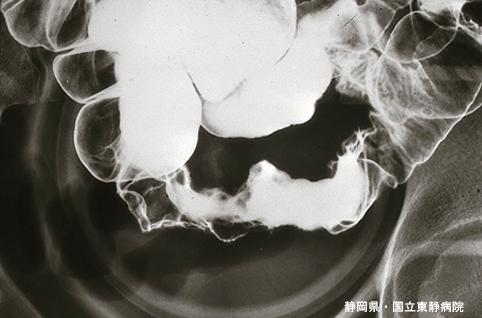

Hemangioma del Intestino Delgado acompañado de sangrado del tracto digestivo (melena) (Caso presentado por Dr. Oseki y Col., Hospital Nacional del Este de Shizuoka, Prefectura de Shizuoka)

Tumor no Epitelial Benigno/Hemangioma

intestino delgado/ileón

Rayos X

40 -